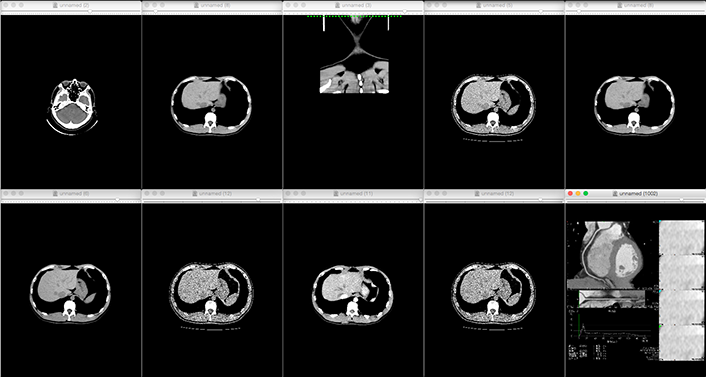

From CT imaging to 3D printer output

- Reads DICOM data obtained from CT imaging into mimics

- Eliminates noise (artifacts) generated by metal and other materials

-

3D data is converted to images or data to see if the region of interest is

We will confirm with the customer that the area of interest has been reproduced.

The customer will be asked to confirm that the area of interest is reproduced in the image or data.If the STL output is available directly from the medical workstation, the above process is eliminated.